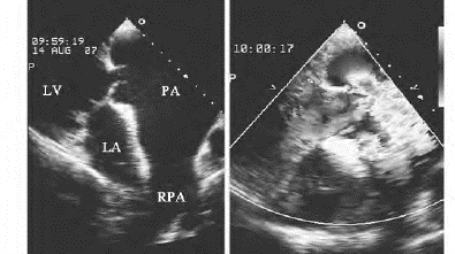

(2)大动脉起源及走行异常:胸骨旁、心尖部及剑突下心室长轴切面和五腔等切面,探头做前后及左右方向连续扫查,可见主动脉起源于靠右前的右心室,肺动脉起源于左后方的左心室(图17-9左图),两大动脉并列上行无交叉。

图17-9 完全性大血管转位二维超声图

左图:胸骨旁心室长轴切面,显示肺动脉起源于左心室;右图:彩色多普勒,显示左心室血流进入肺动脉(见彩图26)

①在二维超声确定解剖结构基础上,显示血流的流向为左心房-左心室-肺动脉(图17-9右图);右心房-右心室-主动脉。